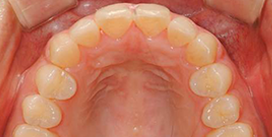

실제 치료 사례

데이몬 교정으로 완성된 아름다운 변화를 확인하세요

비발치 데이몬 교정

치아를 뽑지 않고도 완벽한 치열 개선